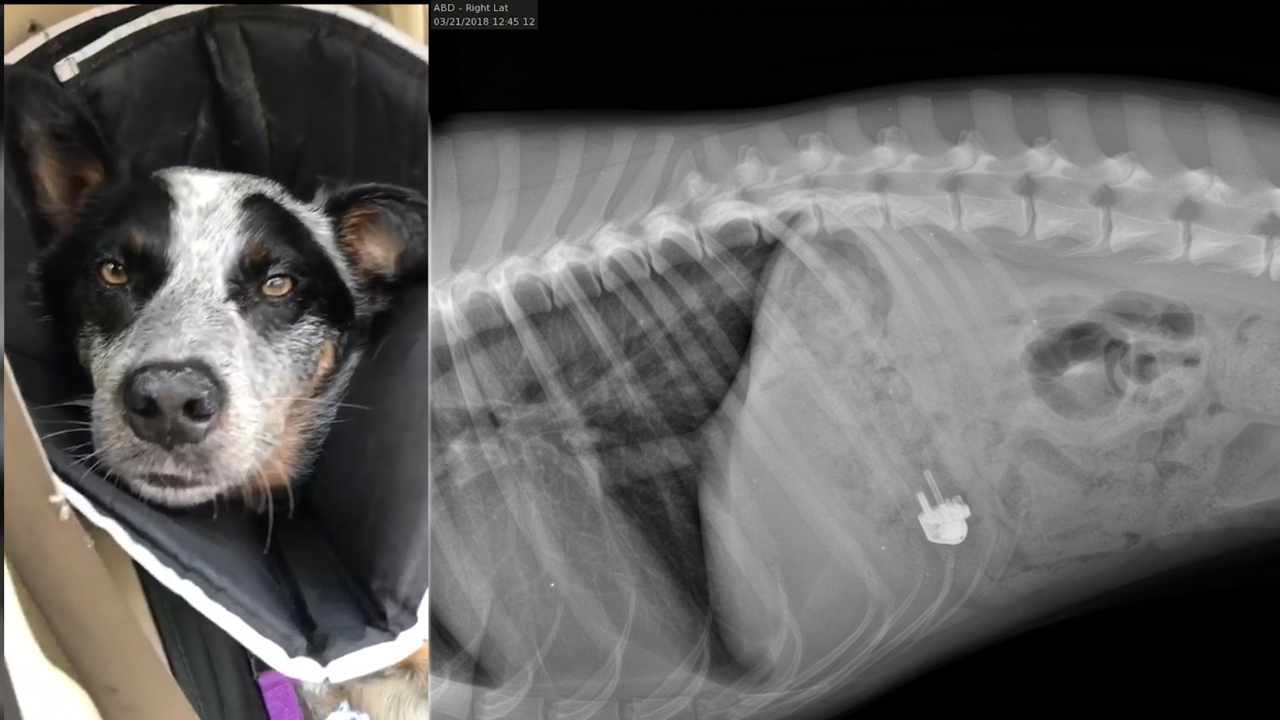

David LauderdaleThink your dog will eat anything? This crazy Hilton Head dog swallowed a lighterUpdated December 19, 2020 at 5:11 PM

LocalMy Hilton Head dog swallowed a cigarette lighter. Here’s how we finally got it backDecember 19, 2020 at 9:00 AM